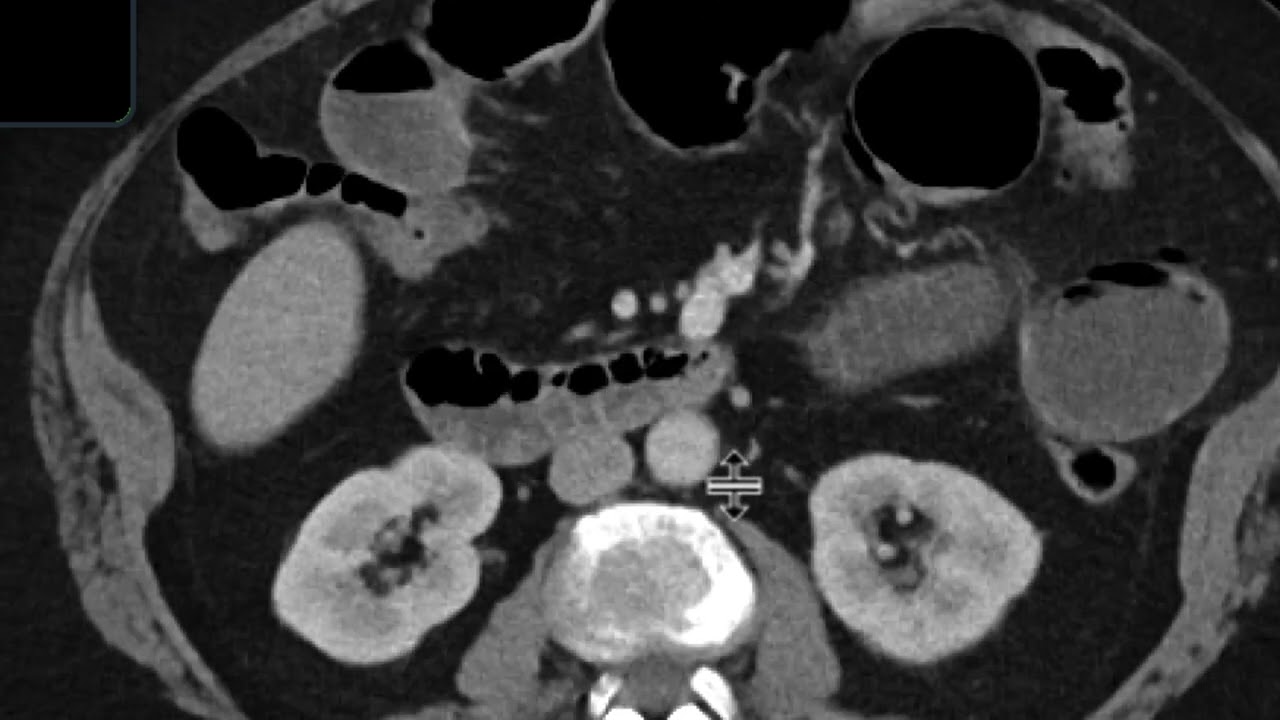

Gallstone Ileus

Описание: Gallstone Ileus is a very rare case of small bowel obstruction. Imaging can help in diagnosis. In the operating room, you may feel a "Mass" so open that piece of small bowel or resect it and visualize the stones. Don't take down the Cholecystoenteric Fistula at the time of the index operation. #absite #generalsurgeryboards